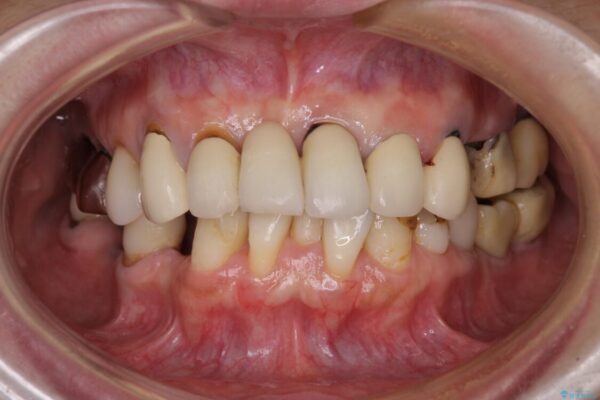

下顎前歯や上顎奥歯などをワイヤー装置により部分矯正を行い、歯列を整えた上でインプラント部分を含めてオールセラミッククラウンにて補綴治療を行うこととしました。

インプラント上の仮歯がボロボロになり、前歯に非常に負担のかかる状態であったため、早急に奥歯の仮歯を修復し、矯正治療、奥歯の補綴治療、前歯の補綴治療と順々に進めて行きました。

治療後

• 放置したインプラントとインビザライン 全顎リカバリー治療 治療後画像